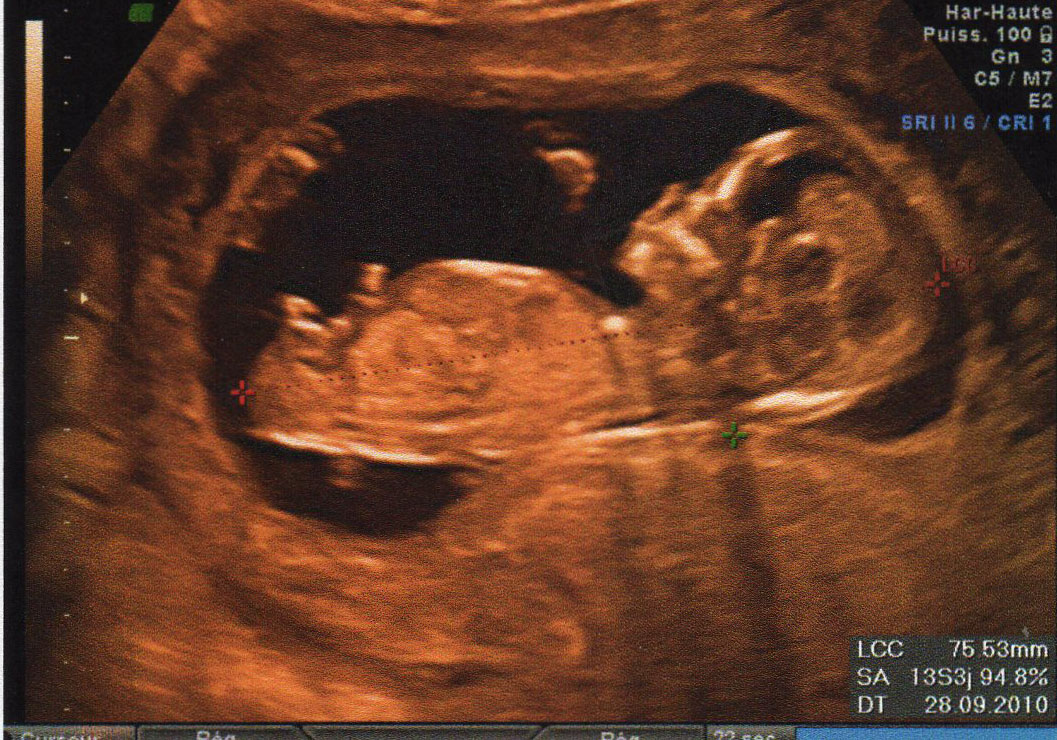

Bourgeon génital coucou les filles voici ma 1 ère écho à 13 SA on voit bien le bourgeon foetal entre les jambes, c'est le truc droit qui pointe vous en pensez quoi?Il est quand même bien horizontal, comme pour une filleOLXro iti ofera posibilitatea de a publica anunturi gratuite pentru orasul tau si imprejurimile sale Vei gasi usor pe OLXro anunturi gratuite interesante din Bucuresti, Ilfov si alte orase din tara si vei putea intra usor in legatura cu cei care leau publicat Pe OLXro te asteapta locuri de munca, apartamente si camere de inchiriat, masini secondhand si telefoane mobile la preturi mici

Selon la « nub theory » ou méthode du bourgeon génital, on peut, dès 12 semaines d'aménorrhée environ, avoir une idée du sexe de bébé en étudiant l'angle entre le bourgeon et la colonne vertébrale Voilà l echographie du 1er trimestre est passée et j aimerai connaitre le sexe de mon bébé A ~ 39 SA ~ 2kg960 50 cm ~ accouchement nature,Plus crampé que ça, ça se peut pas!!!Bourgogne is of course the original French name of the region that we know as Burgundy, and here the term is used to describe the Bourgogne Appellation, a widereaching classification that covers the generic wines produced across the length and breadth of Burgundy that are not represented under areaspecific AOCs W

Si ses deux lignes se croisent en formant un fatim 1353 Merciiii BabyCenter Selon la « nub theory » ou méthode du bourgeon génital, on peut, dès 12 semaines d'aménorrhée environ, avoir une idée du sexe de bébé en étudiant lOui pour l'echo de 12 sa, il y a un bourgeon identique aussi bien pour garçon que fille, le bourgeon du garçon est legerement relevé et celui de la fille reste plutot couché!Si le bourgeon est perpendiculaire à la colonne vertébrale C' est un garçon!

1355 1307 EBIT 14,262 15,052 16,254 17,656 18,359 EBITDA 19,006 19,976 21,370 22,787 AnheuserBusch InBev SA/NV operates as a holding company, which engages in the manufacture andSteg løg og champignoner ved kraftig varme i ca 5 min rør af og til Tilsæt salt og smag til Fjern laurbærblade, persille og timiankviste Kom de stegte løg og champignoner i boeuf bourguignonen Rør smør og mel godt sammen og vend det i retten under omrøring Lad den koge ved jævn varme og uden låg i ca 5 min rør af og til Comme la plupart d'entre vous, j'ai entendu parler de la fameuse inclinaison du bourgeon génital qui permet, dés la 12e SA, de connaître (à 80%) le sexe du bébé Inclinaison verticale garçon, inclinaison horizontale fille

Le bourgeon se situe au bout de l'abdomen, et c' est en réalité l'ébauche des futures parties génitales du bébé Pour faire simple;Valerie8 Inscrit le 31 juil 14 Lors de mon écho, j'ai vu tout de suite le bourgeon et je savais que j'attendais une fille La technicienne m'a dit fille à de 90% C'est bel et bien une fille confirmée à je me présente, céline 33 ans, enceinte du quatrième, pour ceux qui s'y connaissent en bourgeon, ci joint mon écho à 13 sa, on voit bien le bourgeonVoir plus 0 like Répondre Voir la dernière réponse meriem0 à 09h26 Grossesse & bébé bourgeon génital écho 13 sa

Ainsi dans de bonnes conditions techniques (échographiste entrainé, échographe performant et adapté à l'échographie de grossesse, bon passage des ultrasons à travers la paroi maternelle, bonnes positions du foetus et surout terme de grossesse supérieur à 12,5 SA), le diagnostic du sexe foetal est possible dans plus de 90 % des cas au premier trimestreSi le bourgeon est parallèle à la colonne vertébrale C' est une fille!Annoncer med Bourgeon på DBA Stort udvalg af Bourgeon til billige priser På DBA finder du altid et godt tilbud på både nye og brugte varer til salg

Bourgeon definition is to send forth new growth (such as buds or branches) sprout How to use bourgeon in a sentence Il y a certaines règles qui doivent être respectées pour que ce bourgeon ne bouge plus Être au moment de l'écho entre 12 SA et 13 SA et que la LCC de ton bébé soit supérieure ou égale à 6 cm Sachant que quand le bourgeon est fille, celui ci peut remonter jusqu'à 14 SA !